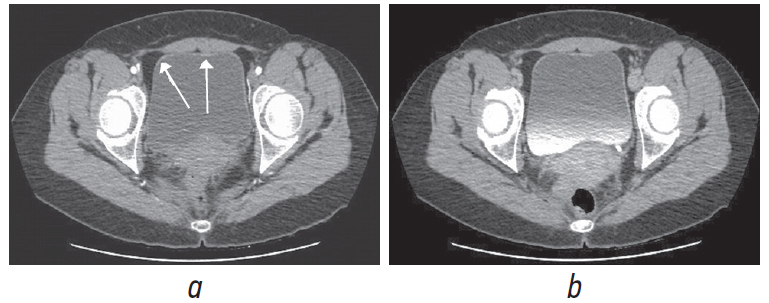

Выполнена МСКТ брюшной полости и органов малого таза с контрастным усилением. Отмечено количественное увеличение мезентериальных лимфатических узлов без их увеличения в размерах. Патологических изменений со стороны мочевого пузыря, мочеточников, почек и тазовой жировой клетчатки не установлено. После тщательного изучения снимков удалось выявить наличие утолщения стенок мочевого пузыря с незначительными, едва заметными плоскими бляшками со стороны слизистой оболочки (рис. 2). Данные образования не накапливают контраст ни при МРТ, ни при МСКТ.

Рис. 2. Мультиспиральная компьютерная томография органов малого таза. Аксиальная проекция: а — нативная, b — с контрастным усилением. Стрелками указаны утолщения стенки мочевого пузыря

Fig. 2. Multislice computed tomography of the pelvis. Axial projection: а – native, b – with contrast enhancement. The arrow indicates the thickening of the bladder wall